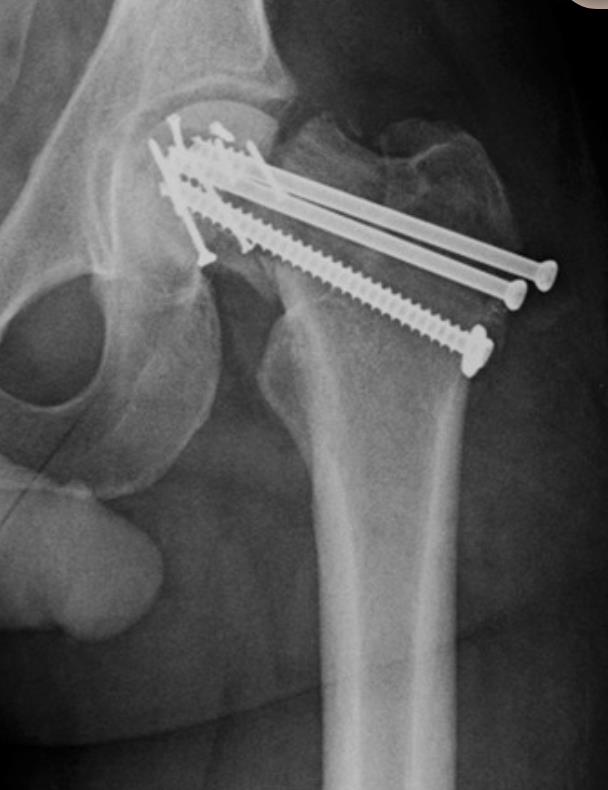

Figure A is the immediate postoperative radiograph of a 51-year-old male who underwent open reduction internal fixation (ORIF) following a Pipkin III fracture of the femoral head and neck following a motor vehicle collision. Which of the following is the most likely outcome for this patient six months following surgery?

Figure A demonstrates the postoperative radiograph of a patient s/p ORIF of a Pipkin III femoral head and neck injury. Illustration A is this same patient 3 months postoperatively showing catastrophic failure which ultimately required THA. Illustration B is a schematic representation of the Pipkin classification.

Pipkin III injuries represent a double insult to the proximal femur and have a high propensity to go on to AVN and failure if treated with ORIF.

Femoral head fractures, fortunately, are uncommon injuries. The primary blood supply to the femoral head is via the medial femoral circumflex artery which arises posteromedially to supply the femoral head. If this blood supply is disrupted, either at the time of injury or the during surgery, avascular necrosis (AVN) ultimately occurs. Femoral head fractures are most commonly classified using this Pipkin classification (Illustration B). Pipkin III injuries result in a "double insult" to the femoral head with a fracture through the femoral head as well as a femoral neck fractures. In a 51-year-old patient, these injuries should be treated with THA as fixation has a very high propensity for catastrophic failure and AVN.

Scolaro et al. review management and radiographic outcomes of patients sustaining femoral head fractures. They report that 7 of 147 fractures were classified as Pipkin III, each of which underwent initial ORIF. Of this selected cohort 100% went on to catastrophic failure and AVN requiring THA. They conclude that these injuries have a high propensity for failure following ORIF.